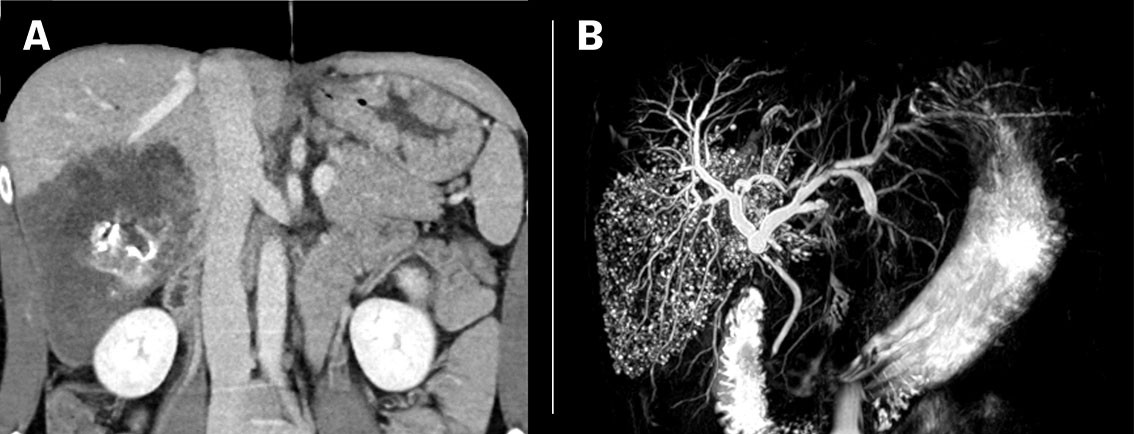

Patient 1: A man in his thirties from Eastern Europe, who had lived for several years in Norway, developed jaundice and pain below his right costal arch. CT abdomen revealed an irregular low-attenuation lesion measuring 13 cm, with central necrosis and calcification in liver segments 6 and 7, while an MRCP test showed that all the involved liver segments were permeated by small cysts (Figure 1). Serological testing detected antibodies to E. multilocularis , and treatment commenced with oral albendazole. He underwent surgery with extensive resection of the right liver. Macropathology confirmed a large, multilocular cyst (Figure 2), and histological examination showed cysts with laminated membranes, necrosis and fibrosis. Radical surgery was not technically possible, and there were residual lesions around the liver hilus and retroperitoneally. The patient is therefore expected to receive lifelong treatment with albendazole.

Diagnosis of alveolar echinococcosis is based on a combination of typical radiological findings positive serology. The final diagnosis is made after histopathological examination and/or PCR analyses of the surgical specimen. Alveolar echinococcosis is classified radiologically according to CT findings (Alveolar Echinococcosis Ulm Classification for Computed Tomography , AEUC-CT ) and MRI (Kodama's classification) (3,4) . The lesions often present on CT as lobulated masses with poorly demarcated margins, irregular central necrosis and scattered calcifications suggestive of a malignant tumour, but the characteristic microcystic components present more clearly on MRI (Figures 1 and 3). MRI is best suited for characterisation and locoregional spread. The diagnosis is generally not based on diagnostic imaging alone, as several other focal hepatic lesions, including premalignant and malignant tumours, can have similar characteristics (5) . An FDG PET scan is useful for initial diagnosis as well as for postoperative monitoring and when relapse is suspected (6) .